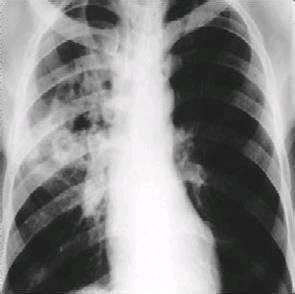

“女兒癆”就是女性青春期結核病。“女兒癆”患者能否結婚生育一向是民間關注的問題。這要根據病情而定,一般來說,結核病活動期最好暫不結婚,重症和排蓖患者更是這樣。因為此時結婚,會使病情惡化。排菌的病人還可能把結核病傳染給愛人,一般女性患者要在疾病康復後兩年結婚為好,或者婚後暫不懷孕。但是肺結核的恢復期或肺結核病情穩定又沒有併發症的病人,經過正規抗結核治療後是可以妊娠的。妊娠期間一定要注意休息和營養。由於結核病病程長,易復發,部分患者有傳染性,因此已婚的“女兒癆”患者還要特別注意不要把病傳染給丈夫。要做到這一點,首先是患者本人要抓緊進行治療,丈夫必須督促妻子進行治療,保證規律用藥,完成規定療程。在強有力的治療方法已經推廣的今天,隔離與消毒已顯得不那么重要,因為積極治療兩周后便可使排菌病人失去傳染性。當然,積極治療和隔離二者相結合則更好。目前也主張進行不住院治療,病人在家中隔離治療,除按醫囑服藥外,最好單人居住一個房間,房間要經常通風,儘量減少病人與健康人頻繁接觸。對病人吐的痰、病人使用的生活用具等須經常消毒處理。當然已經治癒的“女兒癆”也就不存在將病傳染給他人的問題了。